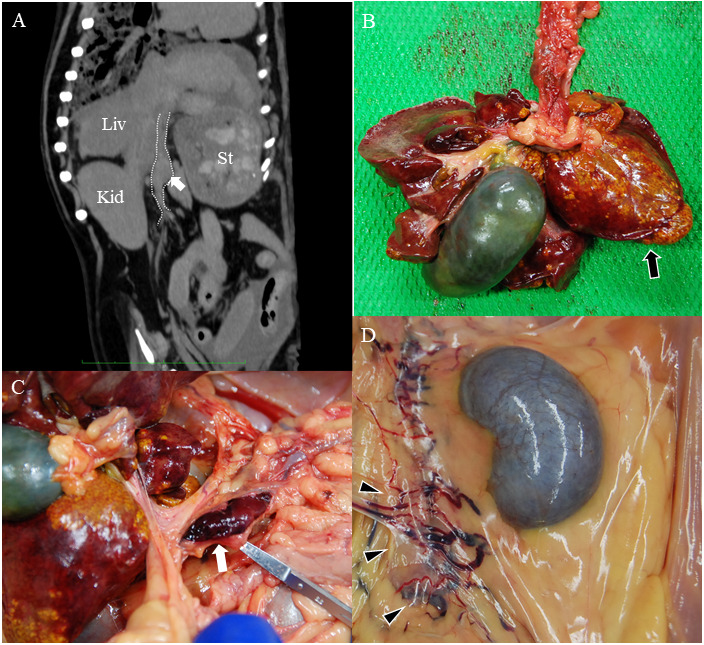

抗凝剂常用于治疗静脉血栓。利伐沙班是一种直接Xa因子抑制剂,在兽医学中广泛用于预防和治疗血栓栓塞。它已被用于管理门静脉血栓形成(PVT)在人类。由于犬伴慢性肝炎(CH)的PVT发病率较低,治疗方法尚未完全建立。本病例报告描述了一只患有CH和腹水的9岁雄性美国可卡犬,可能是由于并发PVT,使用利伐沙班治疗。在利伐沙班和利尿剂治疗期间,患者出现门静脉高压、腹水和水肿的改善。在此,我们报告了第一例使用利伐沙班治疗犬PVT合并CH(用糖皮质激素治疗)的病例。

Anticoagulants are commonly used to treat venous thrombosis. Rivaroxaban, a direct factor Xa inhibitor, is widely used in veterinary medicine to prevent and treat thromboembolism. It has been used to manage portal vein thrombosis (PVT) in humans. As the incidence of PVT with chronic hepatitis (CH) is low in dogs, treatment methods have not been fully established. This case report describes the treatment of a 9-year-old male American cocker spaniel with CH and ascites, possibly due to concurrent PVT, using rivaroxaban. During treatment with rivaroxaban and diuretics, the patient showed improvement in portal hypertension, ascites, and edema. Herein, we report the first case of using rivaroxaban for the management of PVT with CH (treated with glucocorticoids) in a dog.